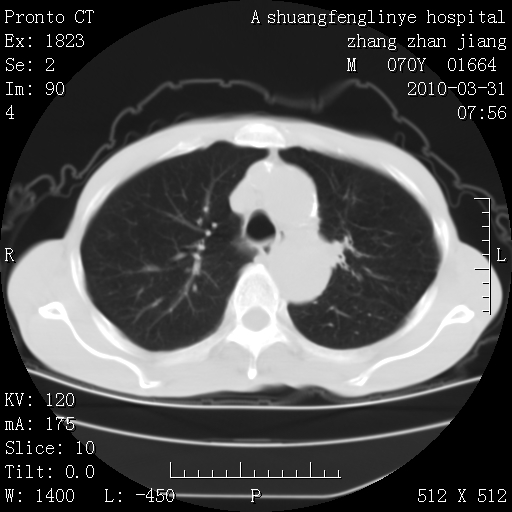

双上肺继发型tb并左上空洞形成,主动脉冠脉钙化。

支持:继发性肺结核伴空洞形成!建议纤支镜检查待出外周围型肺癌可能!

1)两肺上叶继发性肺结核并左肺上叶空洞形成。2)冠状动脉及主动脉钙化。